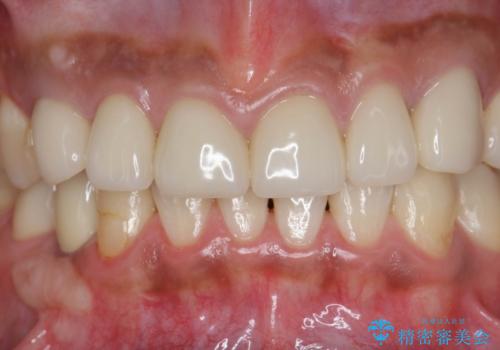

複数箇所コンポジット充填された前歯をセラミック治療

- コンポジットレジンの充填箇所がすり減ってしまい、形の悪くなった前歯の治療を希望され来院されました。

充填部位が大きく、再度充填をするには神経と近くなり抜髄のリスクが高まるため、劣化の少ないセラミックでフルカバーするセラミッククラウン治療を行うこととしました。

- 79.2万円(ジルコニアクラウン×6・仮歯×6)費用は治療当時の料金となります

しかし、経年劣化が早く着色や小さな虫歯が再発しやすいため、ある程度の大きさになってしまった場合セラミッククラウンで置き替えた方が神経を温存し長期的な予後の期待できる治療となります。